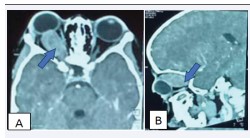

Figure 2: Cerebral CT scan in parenchymal window with injection of contrast medium in axial section (A) and sagittal section (B) showing a right intraconical tumor mass indicated by the blue arrow.